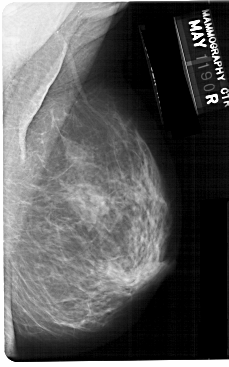

A_1303_1.RIGHT_MLO

RIGHT_CC LINES 5386 PIXELS_PER_LINE 3076 BITS_PER_PIXEL 12 RESOLUTION 43.5 NON_OVERLAY